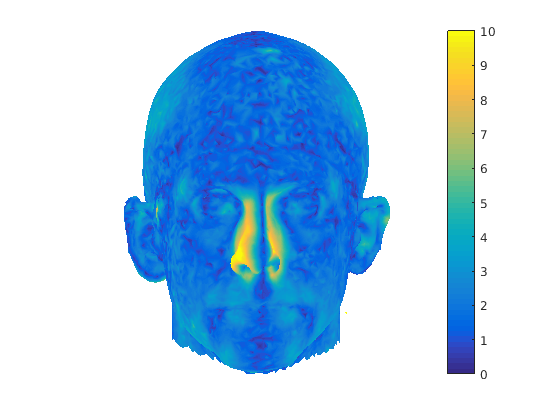

The region that the head scan and its reflection lie in is pre-partitioned into cuboid bins to reduce the computational cost of nearest neighbour search. Fig. 11 show the results of global symmetry plane alignment for 8 adult male samples from the headspace dataset. From observing 100 of these scans we have noticed that the nose, a cartilaginous structure, is often not aligned with the global symmetry plane and regions around the nose area are often rejected as outliers in the trimmed ICP process. As a result, it is not possible to build a good profile model of the face using global symmetry alone, as the ridge of the nose is often not sufficiently well aligned with the global symmetry plane. This motivated us to find the facial contour using local symmetry considerations.

In order to find the facial contour we implemented a piecewise ICP process across the glocal symmetry plane. Each head is first rotated such that its global symmetry plane is coincident with the Y-Z plane. The facial region, as defined by the sparse model fit is then divided into a set of horizontal strips (we use 20mm steps between the nasion and pognion) in the dimension, with the back of the head being cropped out. We apply our trimmed ICP algorithm to each separate strip, so that a local symmetry plane is found for each strip and the facial contour is found by intersecting this sequence of local symmetry planes with its corresponding facial strip. For each strip (index ), we use the strip below and the strip above in the trimmed ICP process in order to reduce the sensitivity of the local symmetry planes to noise. This process is only applied to the face and the cranial region is dealt with as a whole. This is because, in strips, it does not provide sufficient constraints for ICP to lock onto and the two surfaces can slide over each other freely. Fig. 12 shows facial local symmetry contours deviating from the global symmetry plane. Points on the head profile are then extracted by detecting mesh arcs that cross a symmetry plane and linearly interpolating to extract 3D vertices that lie on that symmetry plane.